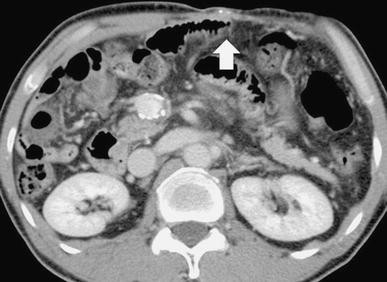

In the venous phase of superior mesenteric arteriography, we observed a collateral vein from the mesenteric varices to small abdominal wall veins (Fig. 2). We performed a surgical incision, and after inserting an 18-gauge plastic needle into an exposed abdominal wall vein we ligated a distal abdominal wall vein. We obtained retrograde CT images through the 18-gauge needle by manually injecting 5 ml of contrast medium (Iopamiron300; Schering Japan, Osaka) to visualize the mesenteric varices and extravasation into the small bowel (Fig. 3). The sclerosing agent was a 1:4 mixture of NBCA and iodized oil (Lipiodol; Laboratoire Guerbet, Roissy, France); this yielded radiopacity. The mixture of NBCA and lipiodol (1 ml) was injected slowly under fluoroscopic monitoring until the mesenteric varices were completely filled. The procedure was terminated when a CT scan acquired just after sclerotherapy demonstrated complete coagulation (Fig. 4).

Retrograde CT images through the 18-gauge needle obtained by manually injecting contrast medium show mesenteric varices (arrow) and extravasation into the small bowel (arrowhead)